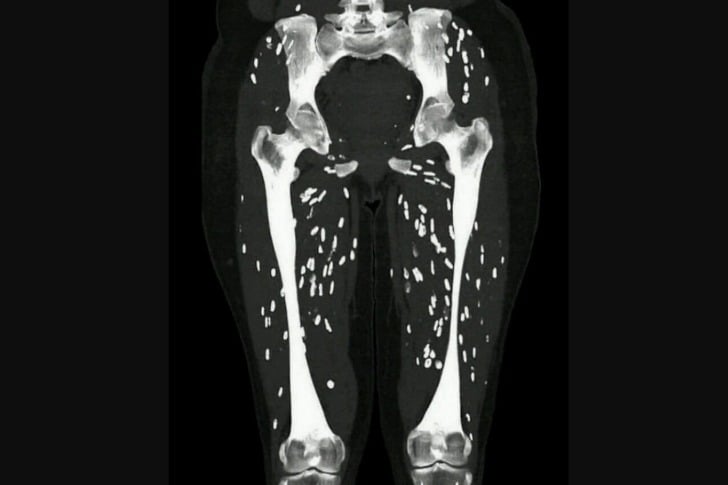

40 Imágenes Médicas Inquietantes Que Son Honestamente Aterradoras #15 Cisticercosis muscular. Se trata de larvas de tenia en el tejido muscular. Advertisements El paciente presenta debilidad y dolor muscular. Advertisements AnteriorSiguiente página Advertisements PREV NEXT PAGE